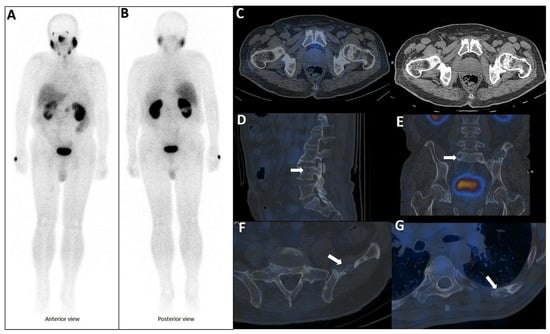

Figure 5.

PSMA scan ruling out the possibility of metastatic prostate cancer. A 73-year-old man was referred for diagnosis/staging, due to mildly elevated serum PSA levels, and a few lytic–sclerotic bone lesions incidentally found in the recent abdominopelvic CT scan. Whole-body 99mTc-PSMA (A,B) and SPECT/CT (C) showed faint PSMA uptake in the prostate gland (PRIMARY score 1) with multiple non-PSMA-avid (white arrows) lytic–sclerotic changes in the L4 vertebra (D), sacrum (E), left iliac (F) and left 6th rib (G). No nodal or visceral involvement was evident. These bone lesions were finally concluded as unrelated pathology to prostate cancer, yet the rare possibility of non-PSMA-avid tumor could not be entirely ruled out.